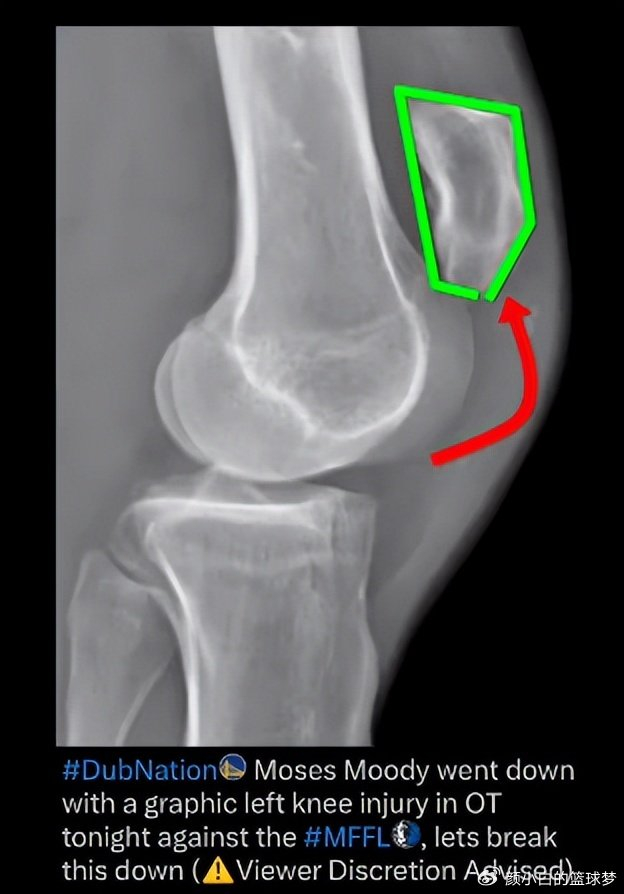

勇士队医疗团队通过核磁共振影像确认,穆迪的伤情属于髌腱部分撕裂,而非更严重的完全断裂。这一诊断结果对球员的康复前景具有关键意义。医学专家Brian Sutterer在播客中解析了伤情机制,指出当肌腱在离心收缩状态下突然承受向心收缩的极限负荷时,极易发生断裂。这种受伤模式与跟腱断裂的机制相似,但幸运的是穆迪的伤情尚未达到完全断裂的程度。

医学界对髌腱损伤的分类具有重要临床意义。髌腱撕裂通常指部分纤维断裂,而完全断裂则意味着肌腱与骨附着点完全分离。这两种情况在治疗方案和康复周期上存在显著差异。根据专业医学资料,撕裂伤的手术难度较低,多数情况下可通过微创技术完成修复。而完全断裂往往需要更复杂的手术操作,部分病例甚至需要开放性手术。